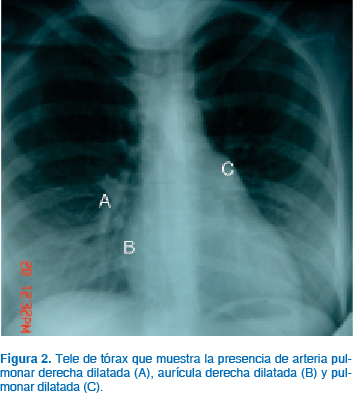

La clase funcional de la New York Heart Association (NYHA) es útil para estratificar el grado de insuficiencia cardiaca y es un enfoque simplificado que consiste en una evaluación funcional básica. En general, las mujeres con clase funcional I o II tienen un pronóstico relativamente favorable durante el embarazo, mientras que aquellas con más limitaciones funcionales significativas tienen mayor riesgo de complicaciones cardiovasculares (Cuadro I).